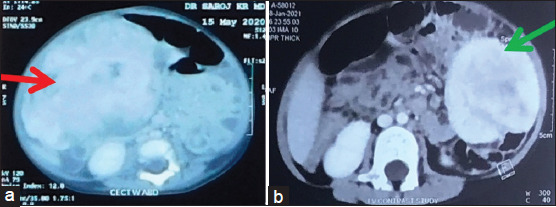

摘要:儿科炎性肌纤维母细胞瘤的临床、放射学和组织病理学特征与该年龄段常见的其他间叶肿瘤重叠,因此给诊断带来了难题。由于其罕见性,确切的特征仍不清楚。在此,我们报告两例此类病例的临床、放射学和组织病理学表现。在这两例病例中,只有在免疫组化后才能确诊。有必要进行进一步的详细研究,以准确确定这些肿瘤的自然病程和预后。

Abstract: Inflammatory myofibroblastic tumour in paediatric patients present with a diagnostic dilemma because of its clinical, radiological and histopathological features overlapping with other mesenchymal tumours common in this age. Because of its rarity, the exact features are still unclear. Here, we are reporting clinical, radiological and histopathological appearances of two such cases. In both cases, the exact diagnosis was confirmed only after immunohistochemistry. There is a need for further detailed study to exactly determine the natural course and prognosis of these tumours.